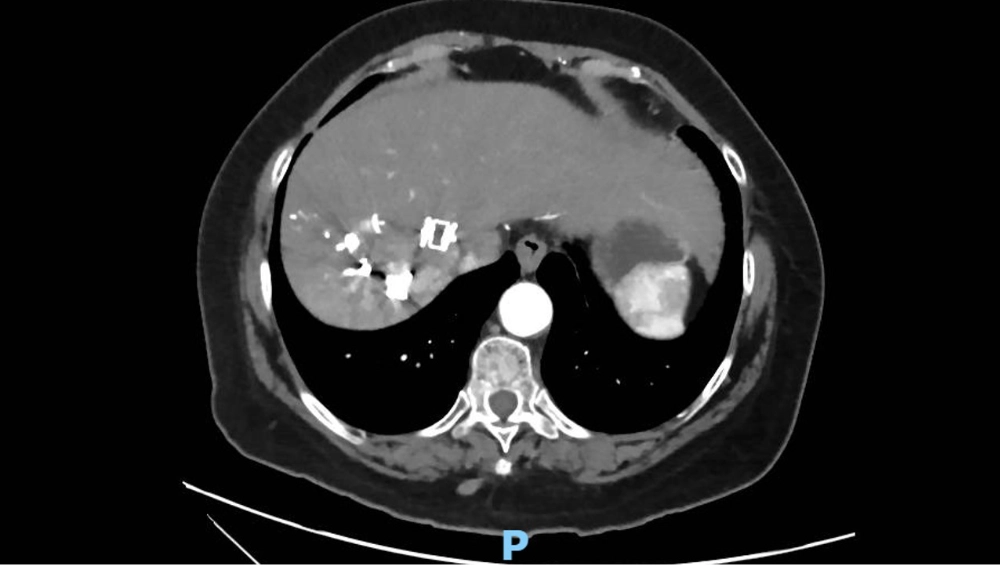

In preparation for surgery, right portal venous and suprahepatic vein deprivation were performed (Figure 2). After venous deprivation, there is an increase in liver remnant from 30% to 42%.

non-crirrhotic-liver-fig2

Figure 2. Axial tomography showing amplatzer and embolization material in right suprahepatic vein and branch to segment VIII of middle suprahepatic.